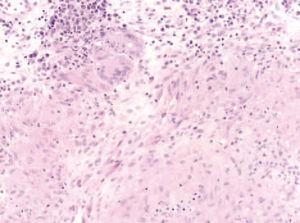

La biopsia de una de las lesiones mostró granulomas epitelioides sin caseificación central en dermis superficial y profunda (fig. 3), así como la existencia de células gigantes multinucleadas (fig. 4).

Figura 4. Hematoxilina-eosina, 20 100.